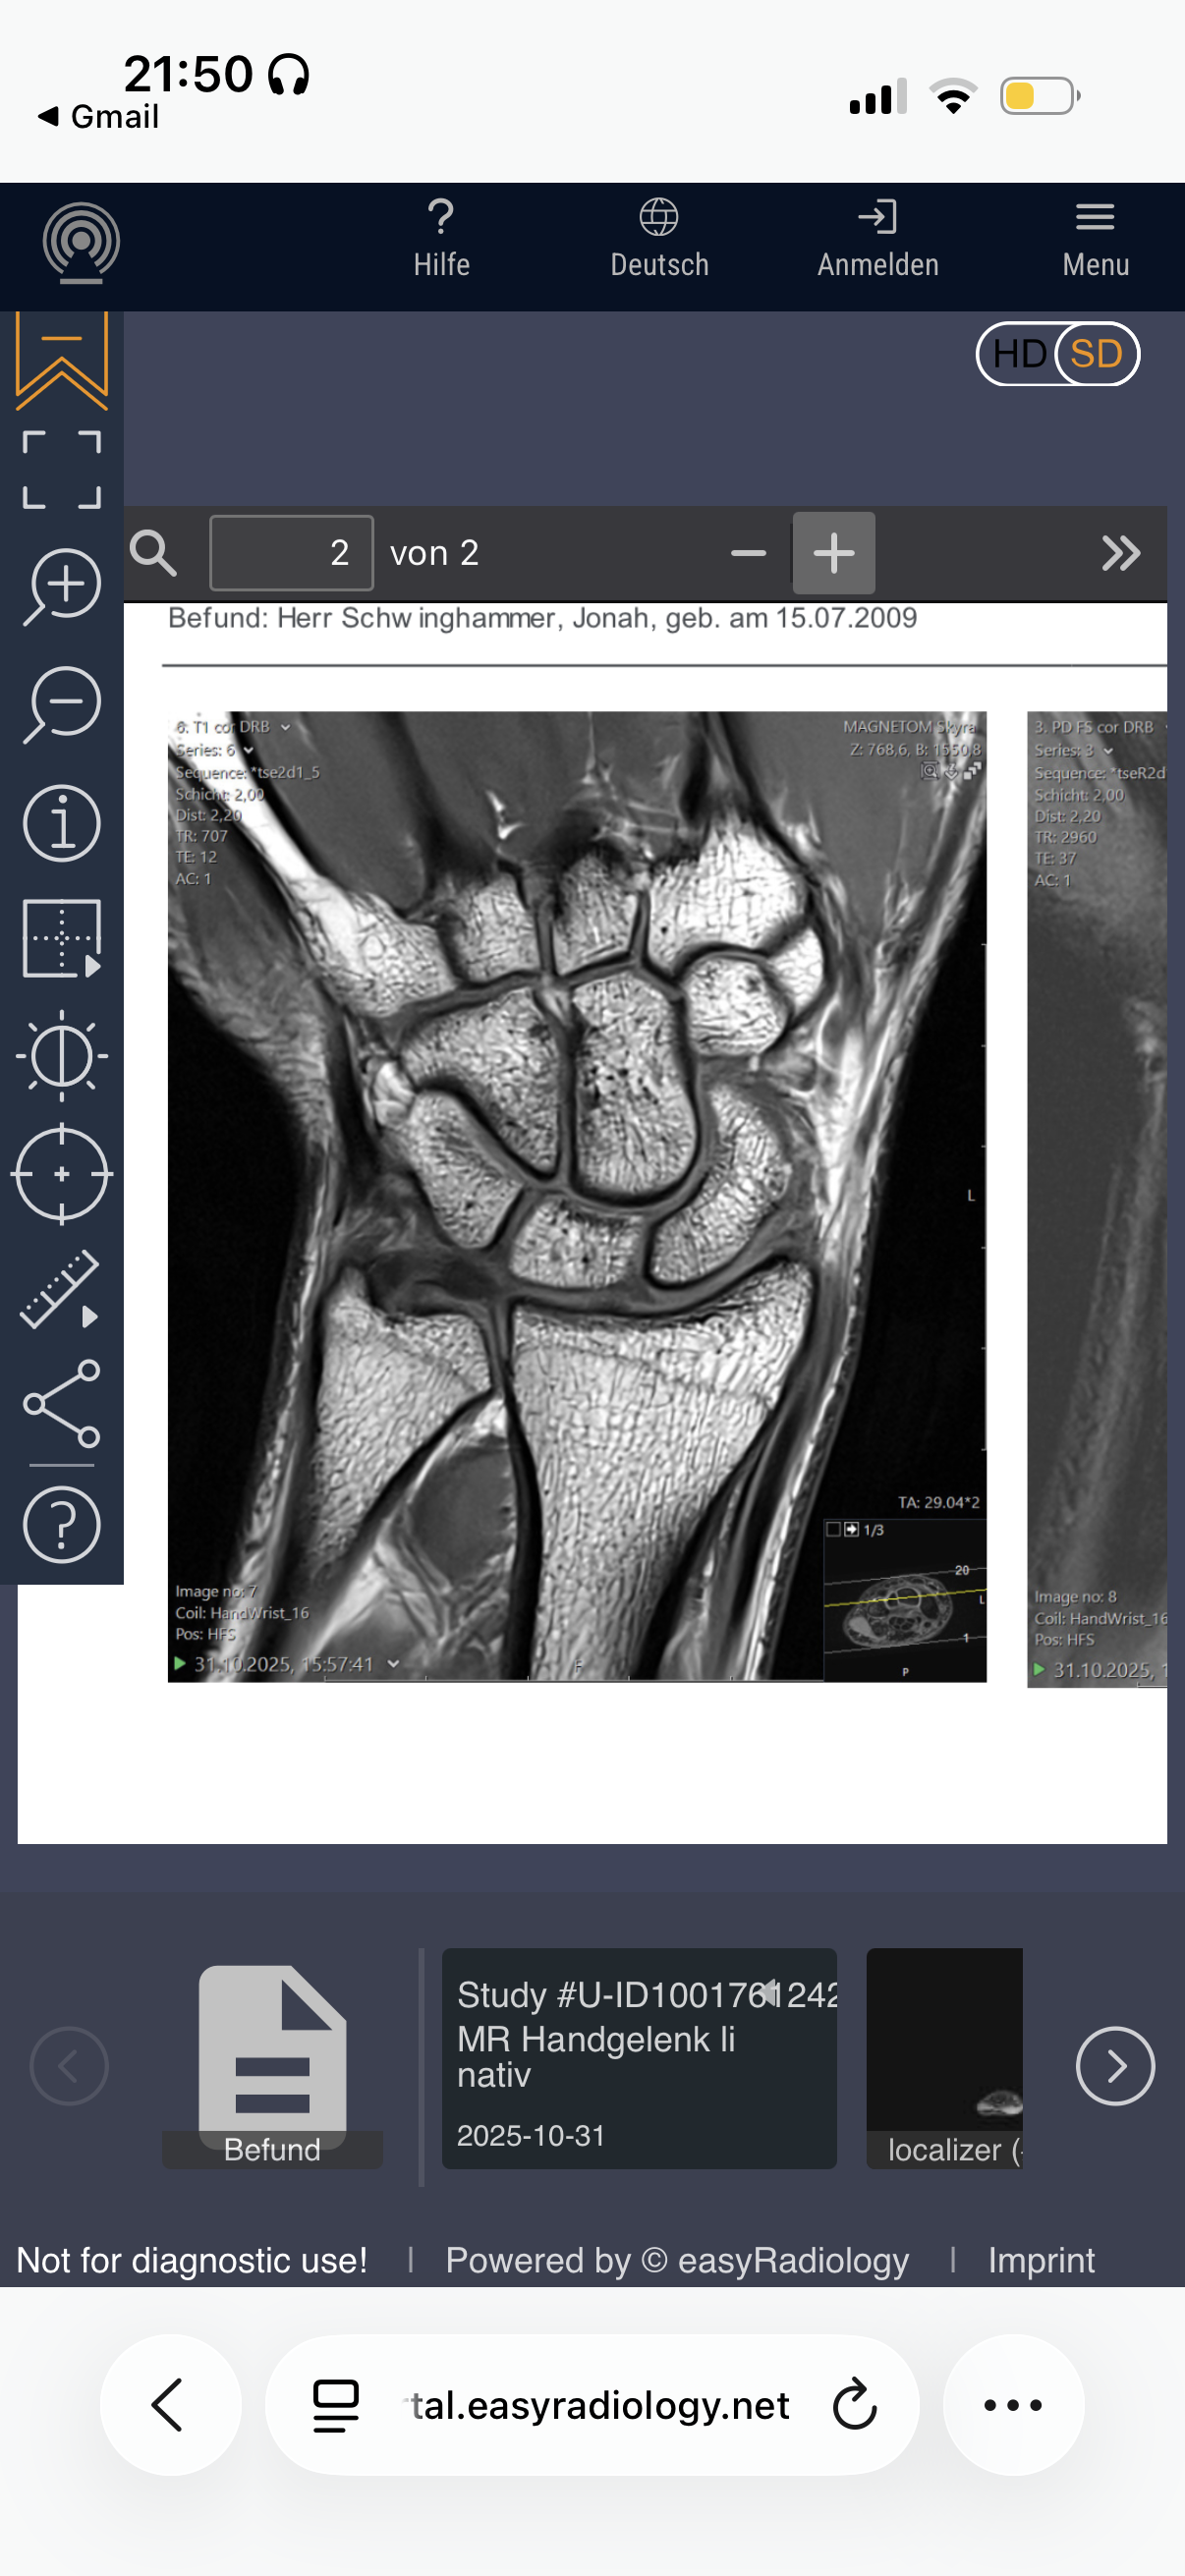

Are my growth plates closed and if not how much growth would hgh + ai help me grow?

Attachments

• IMG_0430.png

IMG_0430.png

Your hands won’t grow, this dosent mean your legs growth plates are closed tho.